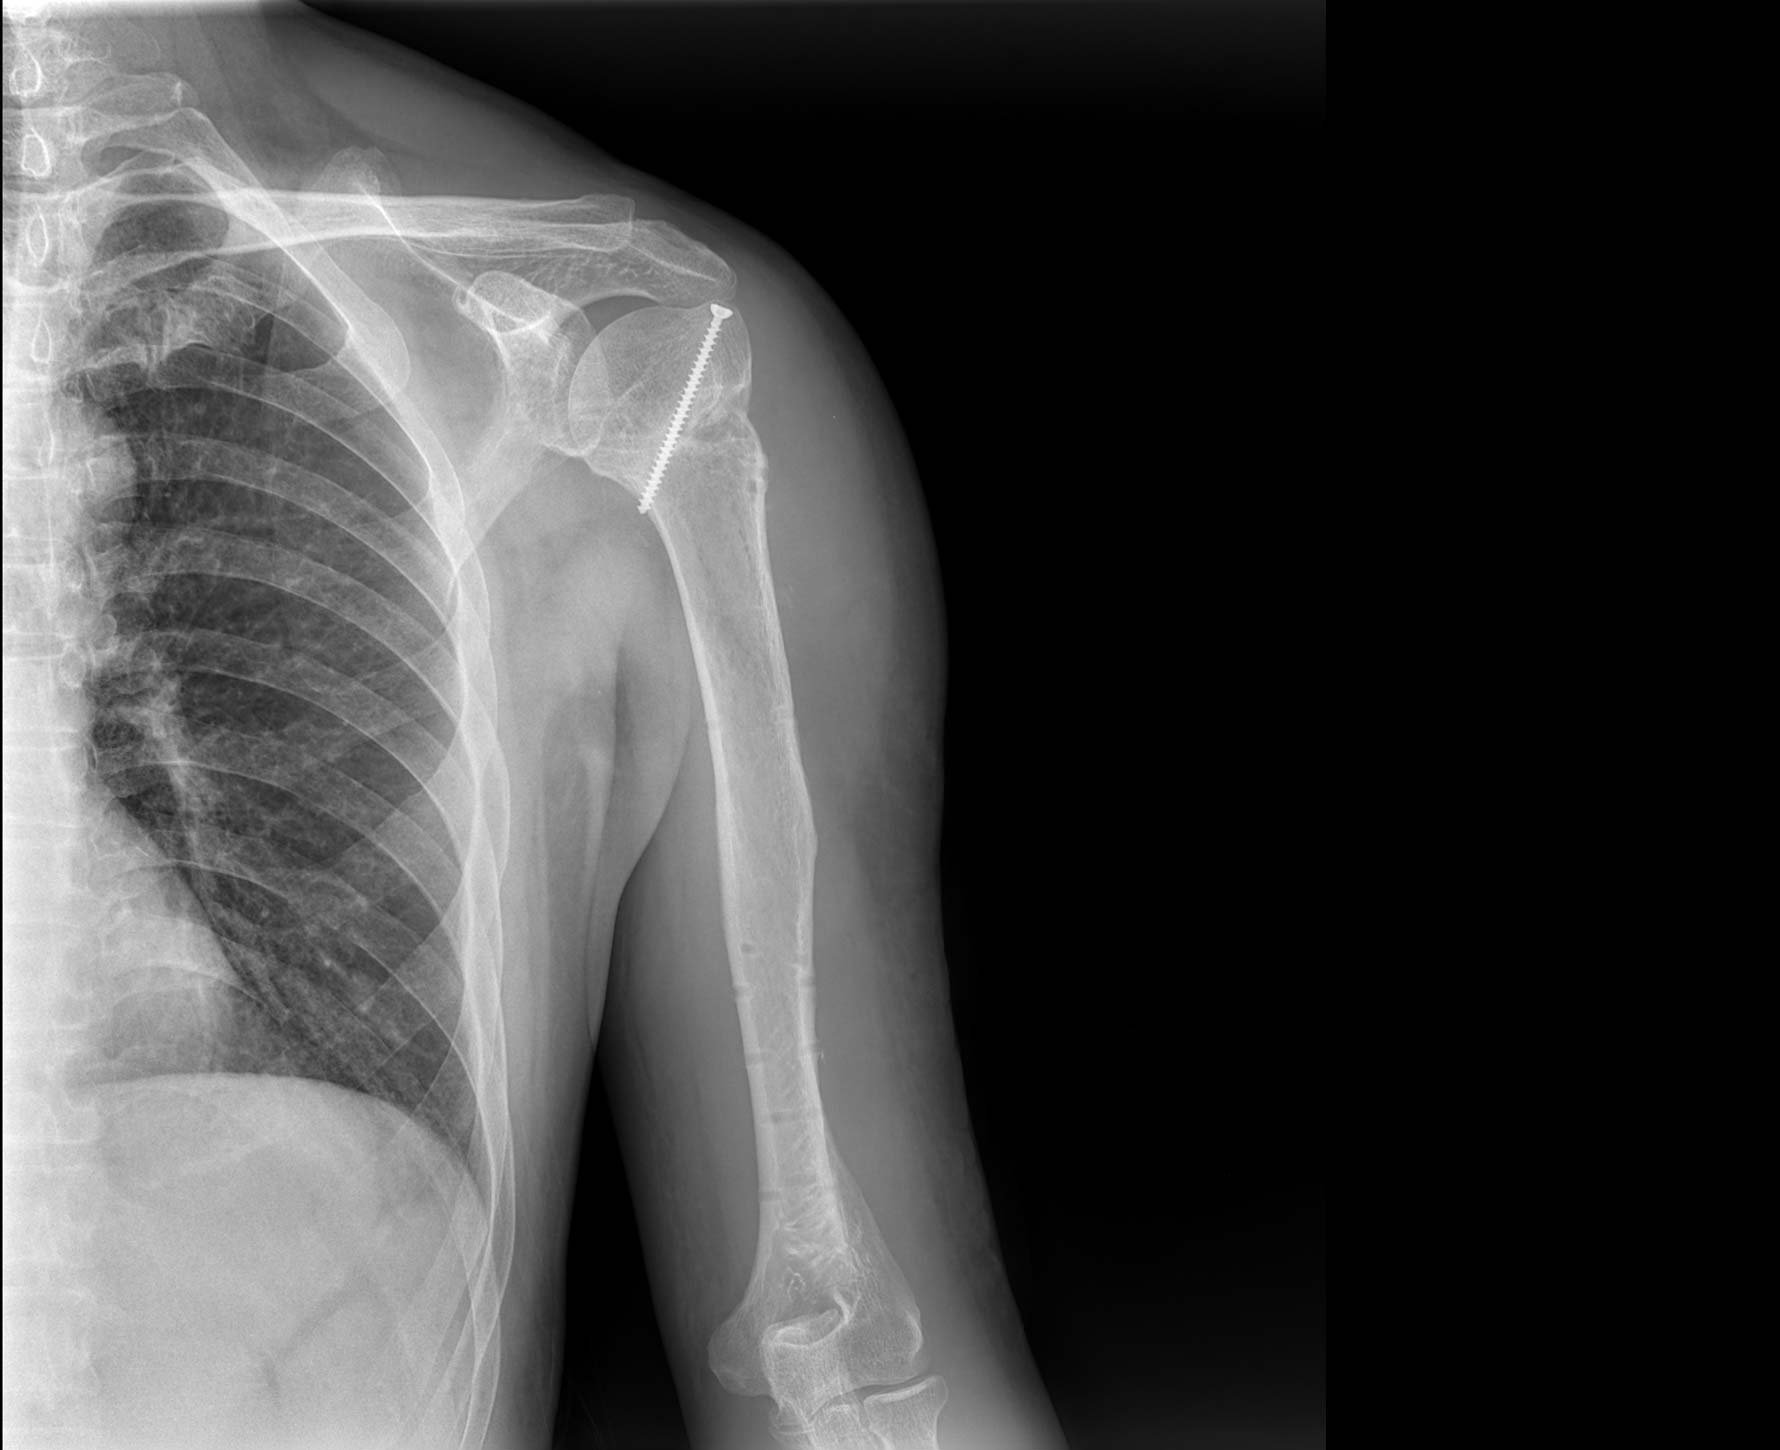

临床图像